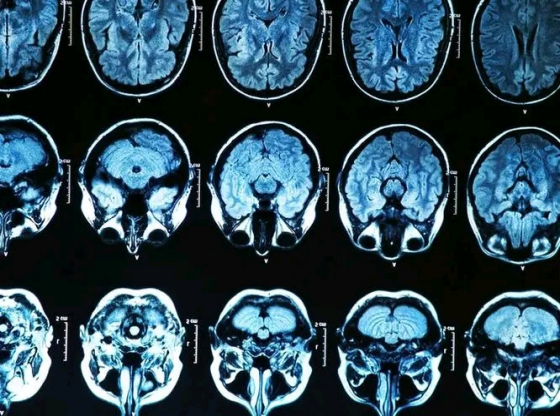

許多50歲以上的人在非三甲以上的機構做檢查和體檢的時候會發現,報告單上有許多見都沒見過,聽都沒有聽說過的疾病。然後他們就把自己置入憂慮和困惑中,以為這些疾病和症狀很嚴重。其實,50歲之後腦CT查出的幾種問題是不需要特殊治療的,也不需要進行特殊的照顧。

第一,老年性的腦萎縮。這種屬於生理性腦萎縮,是老年人常見的生理疾病之一,和腦蛋白舒松有著同樣的病理。讓人患上腦萎縮的原因是年齡的不斷衰老,腦部的組織和細胞不斷地縮小,細胞在形態上有了乾癟的現象。

這些因素都會造成腦萎縮,隨之而來的是腦萎縮誘發人患上一系列的神經疾病和神經性疾病。但是,只要不是在青年人群身上發生的腦萎縮,輕微腦萎縮並不會讓人們有意識喪失和生命喪失的風險。

腦萎縮是人們衰老的自然體現,是我們無法避免的,也是我們無法逃離的。輕微的腦萎縮會在很多中老年人的身上看到,如果陷入腦萎縮給自己帶來的干擾,將會給大腦帶來一定的損傷。只要在生活中注意養護大腦,不要暴飲暴食,不要長期熬夜,就可以起到不錯的調理效果。

第二,普通型腦梗。有些朋友一聽到梗塞這個字眼,就會為他下定義,這是先入為主的做法,也是缺乏理智的做法。實際情況下,普通的腦梗並不是特別嚴重,類似於血管堵塞和毛細血管的堵塞。

患有高血壓和高血脂的人群常常伴隨著輕微腦梗的現象,有血液和血管問題的患者也伴有輕微腦梗的現象。針對腦梗塞來說,醫生會採取比較保守的治療方法,他們不會為我們下確診書。

這也就意味著,透過日常生活中的積極干預和療養,就能夠起到不錯的治療效果,不用為老年性腦梗感到過度擔憂。

第三,腦白質脫髓鞘。腦ct報告單上有一行明顯的字眼,那就是腦白質脫髓掉是否正常。如果做腦ct檢查時發現這一項存在異常,並不需要過度的擔憂。看上去這是一種疾病,其實只要到達了一定的歲數,只要到達了50歲,或多或少會存在這些情況。

輕度的腦白質脫髓鞘在人群中是非常常見的,年紀越大越容易患上這種症狀。許多人根本沒有聽說過腦白質脫髓鞘,對這種症狀也沒有什麼感覺。對於這類患者來說,不需要進行特殊的治療。

當腦白質脫髓鞘處於輕度時,並沒有良好的治療方式可以改善,最重要的就是調整日常作息,把腦子的狀態養好。但如果發展到晚期且非常嚴重的時候,人們會患上一系列的疾病,比如頭痛,偏頭痛和腦神經炎。

上面的幾種現象,在做腦CT的時候會經常發生,也發生在大多數人的身上,我們不用過於擔心,不用讓這些現象給自己帶來太大的壓力,也不用陷入憂慮和困惑中。

這只是一種正常現象,也是一種正常的症狀,腦部有異常並不意味著自己存在著腦部的疾病。隨著年紀的增長,大腦的衰老是我們無法避免的,這種病症不是病理性的疾病。